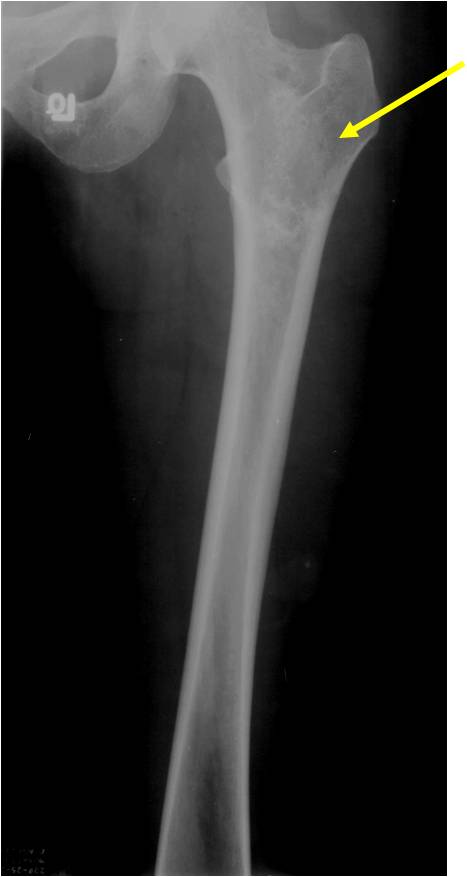

Ring and Arc Calcifications Minimal Endosteal Scalloping Cortex Intact No Soft Tissue Component No Periosteal Reaction

Ring and Arc Calcification No Endosteal Scalloping